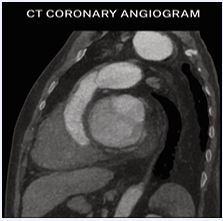

A 49-year-old male presented with complaints of intermittent palpitations for three years, increasing on exertion and associated with sweating. Clinical evaluation revealed atrial fibrillation with a controlled ventricular rate. Baseline echocardiography demonstrated a large mass in the interatrial septum measuring approximately 5.2 × 3.0 cm, suggestive of a cystic lesion with internal septations. Transesophageal Echocardiography (TEE) confirmed a large mass arising near the non-coronary sinus of Valsalva, raising suspicion of aneurysm with internal thrombus. Coronary angiography showed mild coronary artery disease. Cardiac MRI demonstrated an aneurysmal dilatation of the non-coronary cusp of the aortic sinus measuring 4.3 × 3.1 cm with eccentric mural thrombus, causing compression on the left atrium. No myocardial edema, perfusion defect, or late gadolinium enhancement was noted. CT coronary angiography further delineated a saccular aneurysm from the non-coronary sinus measuring 3.8 × 3.8 × 5.6 cm with non-enhancing thrombus, indenting the left atrium and right pulmonary vein. Calcified plaques causing mild luminal narrowing were noted in the left main coronary artery and left anterior descending artery. The total calcium score was 420. The cardiothoracic surgeon had assessed the operative risk to be significantly high in view of the patient’s very low body weight (40 kg), raising concerns regarding perioperative morbidity, hemodynamic instability, and postoperative recovery. These factors were clearly explained, and although surgery was advised, the patient declined the procedure after understanding the associated risks. In view of the high surgical risk and the patient’s informed refusal, we adopted a conservative management strategy. The patient was managed with rate control for atrial fibrillation and remains stable on follow-up (Figures 1-3).

Figure 3 Cardiac MRI demonstrating aneurysmal dilation of non coronary cusp with eccentric thrombus, no myocardial edema, and preserved LV systolic function.